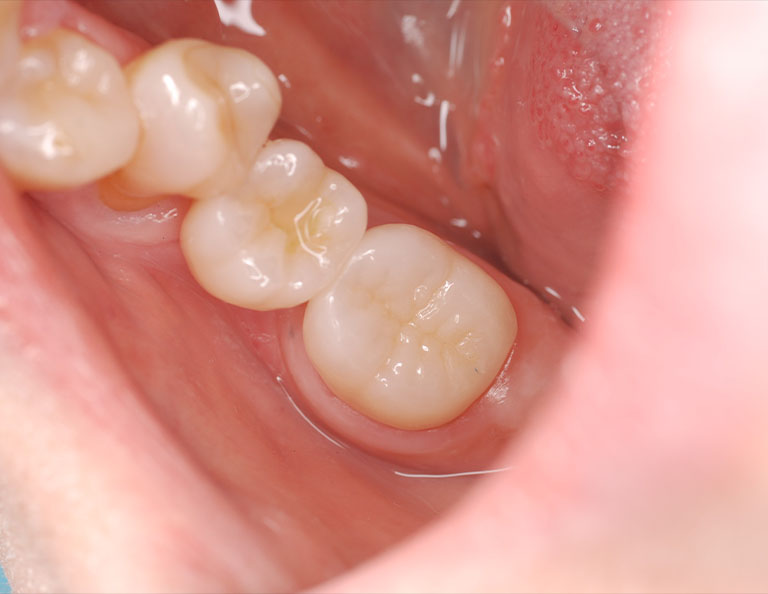

右下第二大臼歯が腫れたということで来院されました。レントゲンおよびCT撮影をしたところ、根っこの先および周囲が黒く抜けており、神経が死んでしまい膿が溜まっている状態でした。被せ物を外したところ歯にヒビが確認できましたが、何とか保存できると判断し、樹脂で補強した後、ラバーダム防湿下で根管治療を行いました。 |

状態が改善したことを確認し、最終的な被せ物を装着しました。